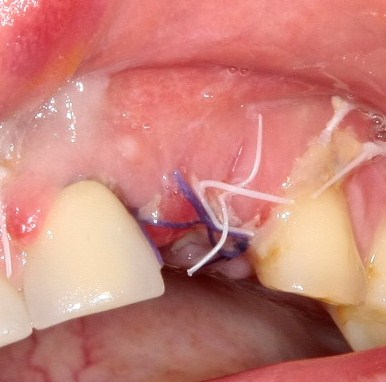

И швы:

Как и на первом этапе, мы делаем назначения и даем рекомендации, а также в течение нескольких дней контролируем состояние послеоперационной раны.

Вот так она выглядит через день после операции:

Разумеется, пациентку никто не оставляет без зуба. Если Вы обратили внимание, то заметили справа на правой фотографии остатки металлического ретейнера. С помощью него к соседним от дефекта зубам фиксируется адгезивная коронка. Она, конечно же, не дает возможности нормально кусаться, но зато отлично маскирует отсутствие зуба. Таким своеобразным временным протезированием пациентка пользуется от начала и до конца лечения.